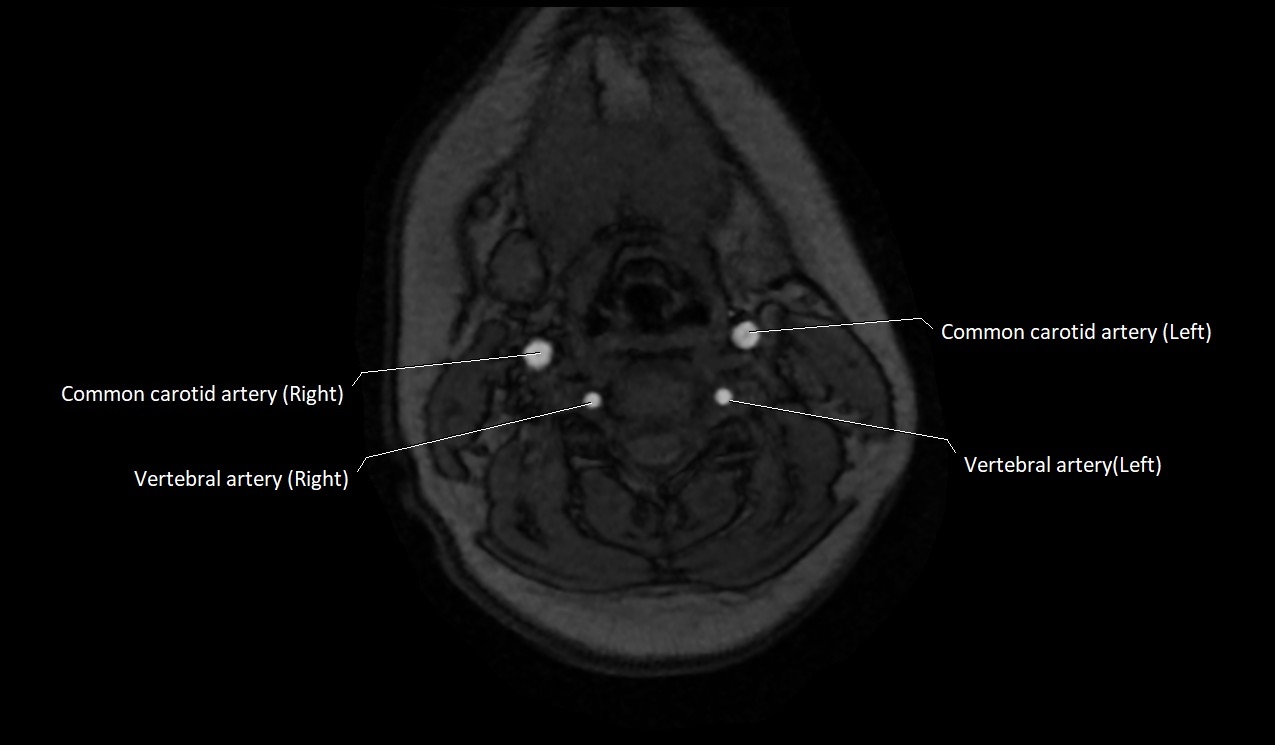

MRI images

image